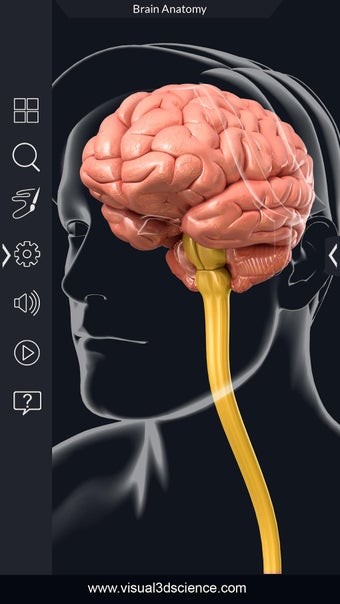

برنامج تشريح الدماغ Pro هو تطبيق تعليمي لدراسة تشريح الدماغ البشري. تم تصميم هذا التطبيق لكل من الطلاب الطبيين والجمهور العام. يتيح للمستخدمين استكشاف الدماغ من جميع الزوايا وعرض التشريح بطرق مختلفة. إنه أداة سهلة الاستخدام تتيح للمستخدمين تدوير 360 درجة والتكبير والتصغير وتحريك الكاميرا حول نموذج ثلاثي الأبعاد واقعي للغاية. يتيح للمستخدمين القدرة على تحديد الأجزاء وعرضها بالأشعة السينية وإخفائها وإظهارها وعرض الرسوم المتحركة في الوقت الحقيقي والرسم أو الكتابة على الشاشة ومشاركة لقطات الشاشة ونطق الصوت لجميع مصطلحات التشريح والمزيد. إنه تطبيق تعليمي مجاني.